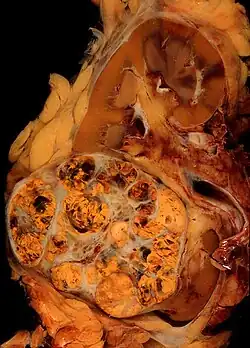

Anatomopathologie

Elle est basée essentiellement sur l'examen anatomopathologique de la pièce chirurgicale d'exérèse, la biopsie n'ayant que peu d'utilité. La classification anatomo-pathologique des tumeurs du rein est la classification UICC.

90 % des cancers du rein sont des carcinomes à cellules rénales, répartis en différents types histologiques[13] :

- Carcinome à cellules claires du rein (80 à 90 %)

- Carcinome papillaire subdivisé en Carcinome papillaire de type 1 et Carcinome papillaire de type 2[24] (10 à 15 %)

- Carcinome à cellules chromophobes (4 à 5 %)

- Carcinome des tubes collecteurs

- Carcinome inclassable